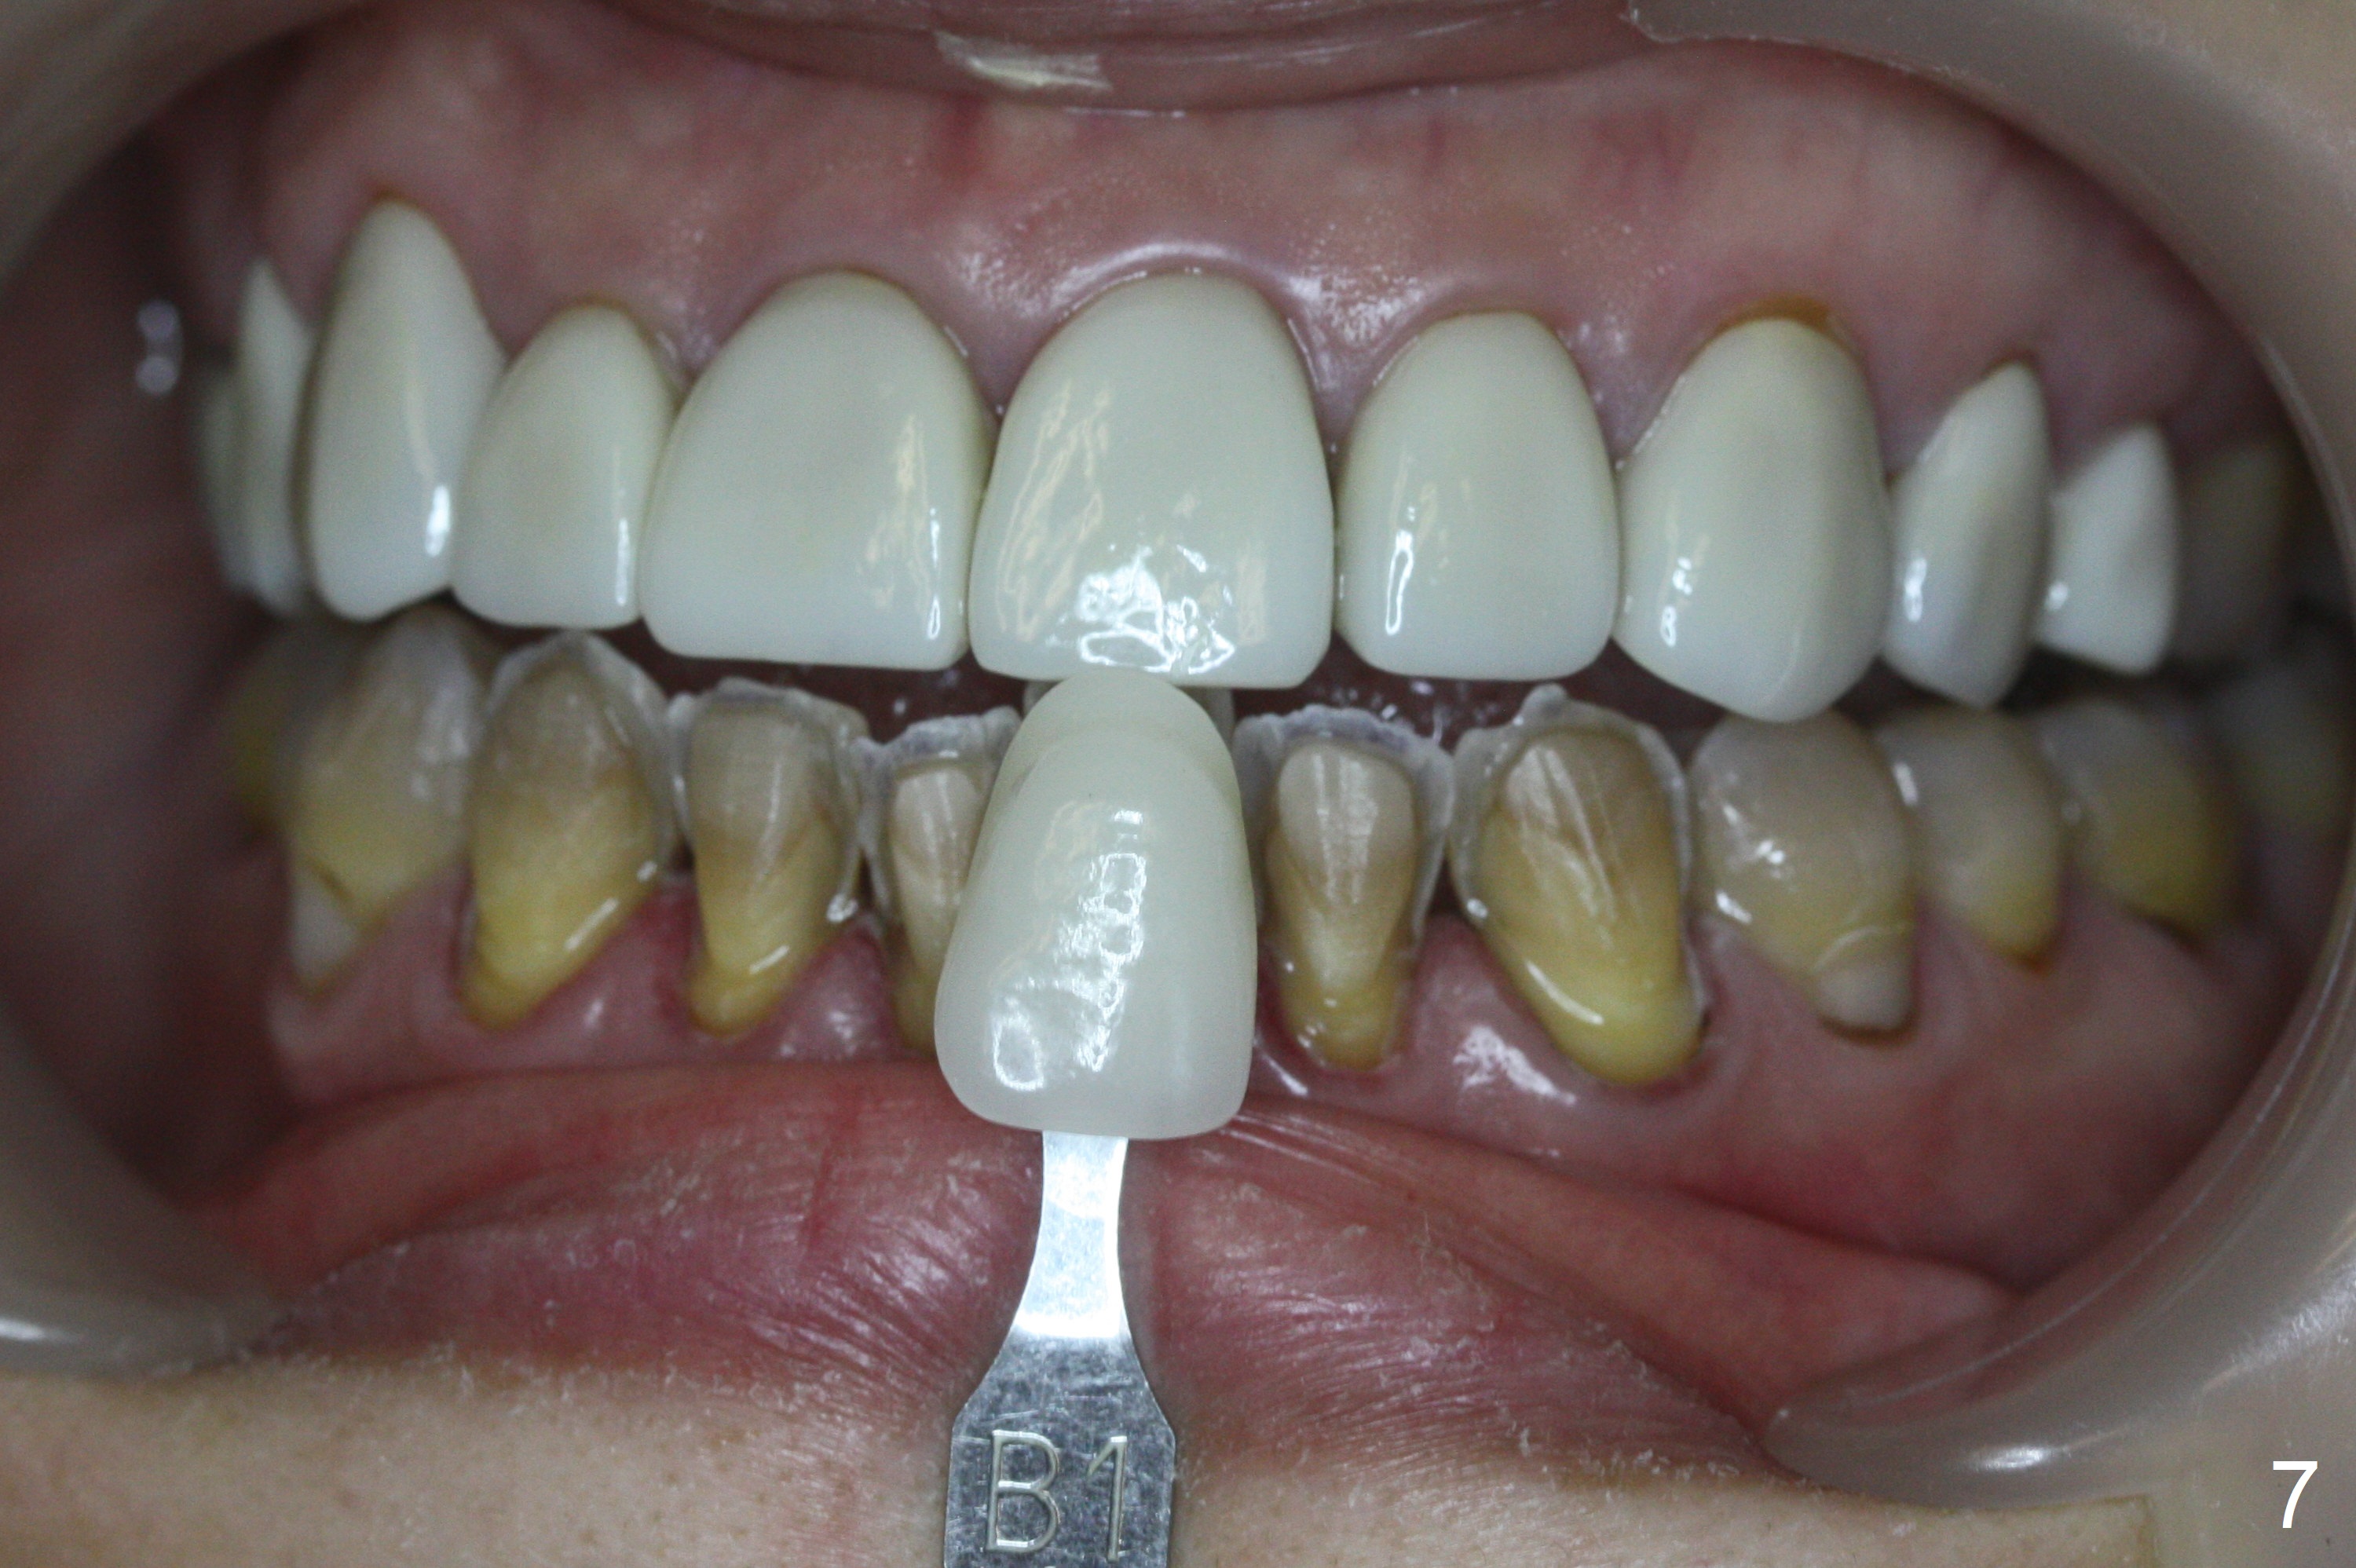

After prep (Fig.5), stump shade is chosen (Fig.6). Although B1 was selected for the upper veneers (Fig.7), the patient prefers to have A1 for the lower ones (Fig.8).